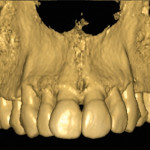

Autotrapianto di ottavo incluso a sostituzione di un settimo irrimediabilmente compromesso: case report

Luca Boschini1

Michele Melillo2

1Odontoiatra, libero professionista, Rimini

2Odontoiatra, libero professionista, Manfredonia (FG)

Specializzato in Chirurgia odontostomatologica presso l’Università G. D’Annunzio di Chieti

Riassunto

I trapianti dentali sono un capitolo...